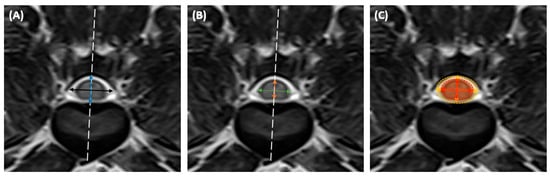

2.2. Measurements and Analysis of MRI